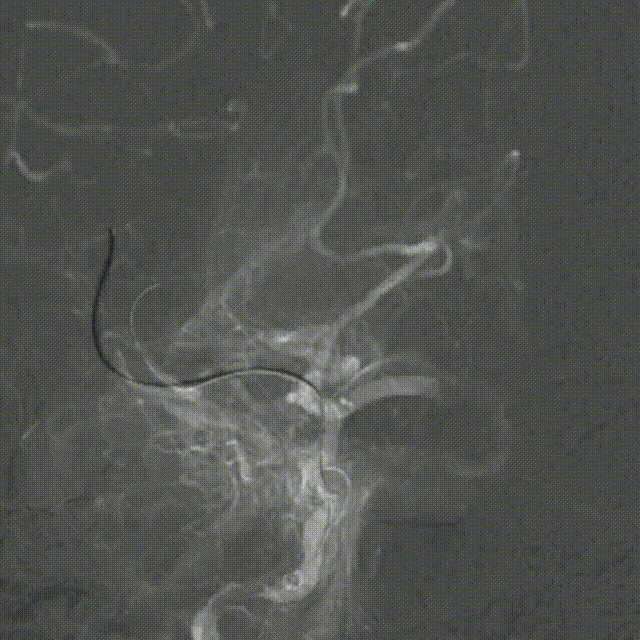

释放Syphonet®取栓支架 5*35mm,造影显示:支架释放效应可疑阳性。

造影:考虑局部血栓可能。

再次释放Syphonet®取栓支架 5*35mm,造影显示:支架释放效应阳性。